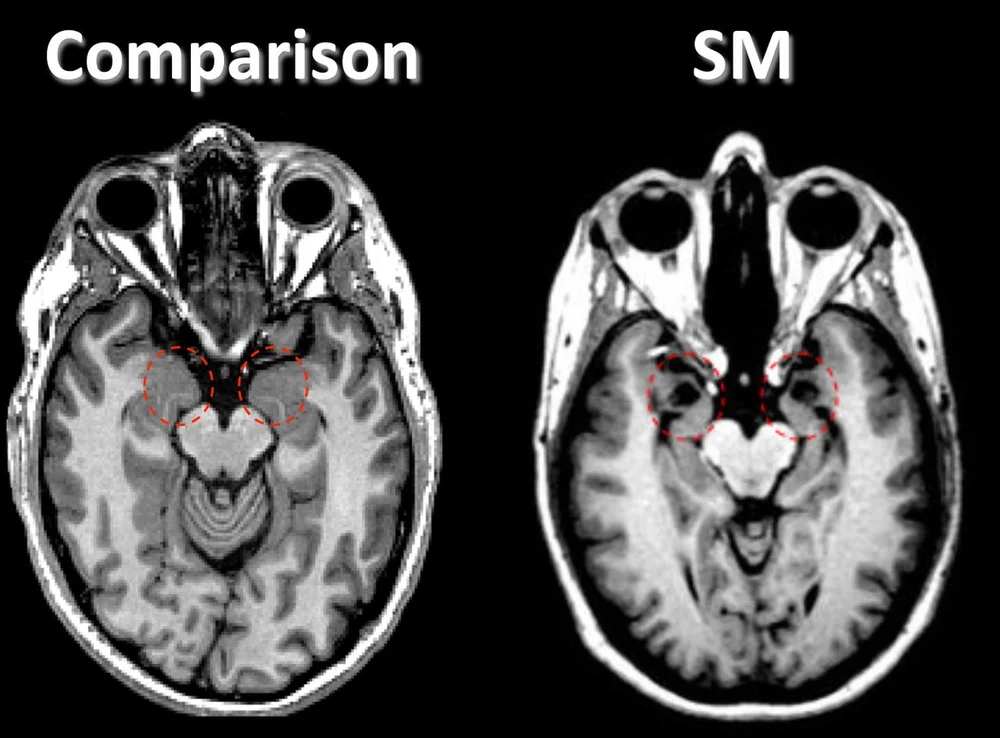

Diskriminierung bezeichnet eine Benachteiligung oder Herabwürdigung von Gruppen oder einzelnen Personen nach Maßgabe bestimmter Wertvorstellungen oder aufgrund unreflektierter z. Charakteristisch ist das Auftreten von Heiserkeit in der frühen Kindheit sowie eine Vergröberung und eine Vergrößerung von Zunge und Lippen sog. Das Urbach-Wiethe-Syndrom auch Lipoidproteinose oder Hyalinosis cutis et mucosae ist eine sehr seltene genetisch bedingte Erkrankung autosomal-rezessiv die mit Hautveränderungen Schleimhautveränderungen Heiserkeit und Verkalkungen der Amygdala eines Teils des Limbischen Systems einhergeht und im Jahre 1929 erstmals als.

Urbach-Wiethe-Syndrom und Chromosom 1 Mensch Mehr sehen Diskriminierung. The Urbach-Wiethe syndrom is an hereditary disease which start during early childhood distinguishable by a lipoglycoproteinosis which affects the skin mucosae and also the eyes with cyst formations in the lids marginal drusen of Bruchs membrane. Cutis et mucosae Urbach-Wiethe-Syndrom Englisch. Ela está associada com alterações da pele alterações na membrana mucosa rouquidão e calcificações da amígdala parte do sistema límbicoA expectativa de vida das pessoas afetadas geralmente não é reduzida. Diskriminierung bezeichnet eine Benachteiligung oder Herabwürdigung von Gruppen oder einzelnen Personen nach Maßgabe bestimmter Wertvorstellungen oder aufgrund unreflektierter z. Nenhum exemplo encontrado considere adicionar um. Veja exemplos de tradução de Urbach-Wiethe-Syndrom em frases ouça a pronúncia e aprenda gramática. Urbach-Wiethe-Syndrom und Diskriminierung Mehr sehen Dysphonie. Suffers from fear-of-success syndrome.

Aqui a tradução alemão para inglês do Dicionário Online PONS para Urbach-Wiethe-Syndrom. Saiba como pronunciar Urbach-Wiethe-Syndrom em Alemão com a pronúncia nativa. Diskriminierung bezeichnet eine Benachteiligung oder Herabwürdigung von Gruppen oder einzelnen Personen nach Maßgabe bestimmter Wertvorstellungen oder aufgrund unreflektierter z. A complex of symptoms indicating the existence of an undesirable condition or quality. Ela está associada com alterações da pele alterações na membrana mucosa rouquidão e calcificações da amígdala parte do sistema límbicoA expectativa de vida das pessoas afetadas geralmente não é reduzida. Heiserkeit Vergrößerung von Zunge und Lippen. A distinctive or characteristic pattern of behavior.